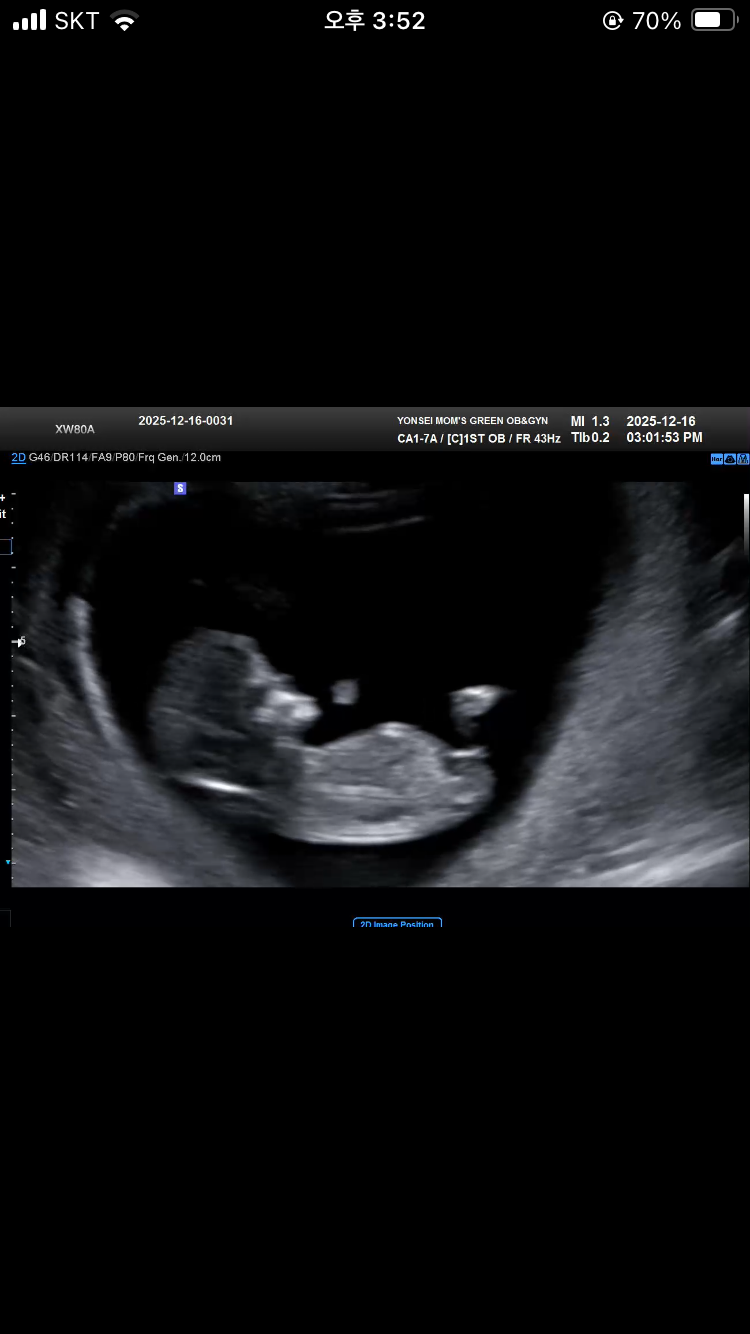

11주 3일 초음파 각도법 성별 봐주세용!

11주3일 초음파에요~ 각도법 잘 보시는 분 계시면 성별 댓글 많이 달아주세요! ㅎㅎ